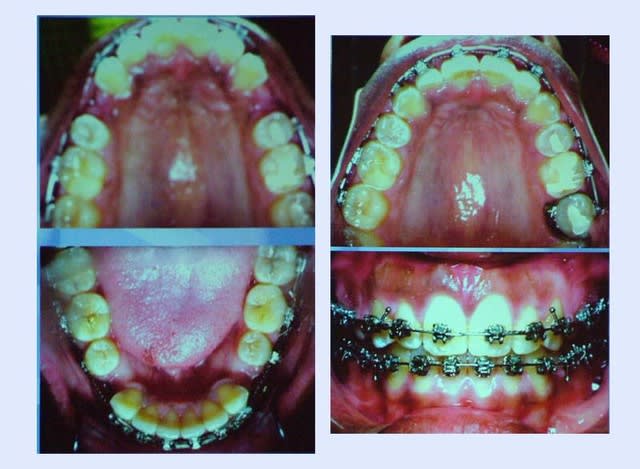

cas traité par A. Bagden, présenté en 2005

A. Bagden a traité ce cas facilement

en utilisant :

au maximum la conséquence des extractions qui est de creuser le profil

comme quoi,

on peut déplacer des canines, rien qu’avec les forces biologiques musculaires

il n’a fait que guider les forces musculaires, il a presque laissé faire

ce n’est pas le résultat d’une mécanique surajoutée aux forces musculaires qui peut être à contrario, ou bloquer les dents que l’on veut déplacer car on a négligé ces forces musculaires

cela remet aussi en question la notion d’ancrage

2 postulats bousculés :

on ne peut pas déplacer des canines

nécessité de l’ancrage fort